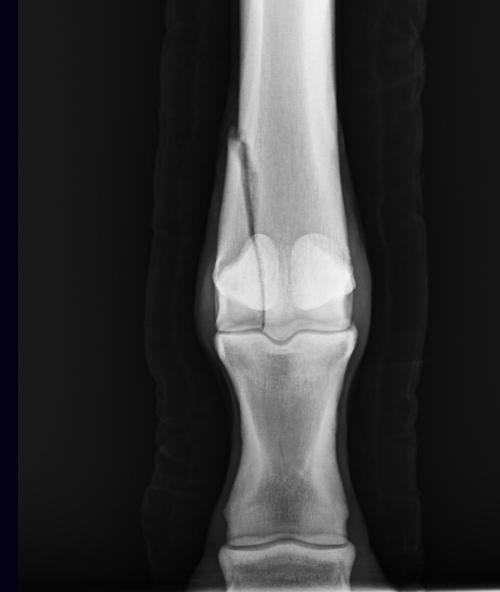

Fractures of the condyle—the bottom or distal end of the cannon bone that fits into the fetlock joint—can also occur.

“Condylar fractures are something I see quite a bit as well,” Allday says. “These usually occur in racing Thoroughbreds and are found typically after fast workouts or races.”

“Ultimately, this injury can become a condylar fracture,” Freeland explains.

Condylar fractures Veterinarians once considered a condylar fracture a career-ending injury. Thanks to advancements in equine surgery, however, this is generally no longer the case—and these cases customarily do need surgical repair, says Freeland. Ultimately, fracture configuration and healing at the joint surface influence the horse’s prognosis.

“Surgery can most commonly be performed with a couple screws placed across the fracture line near the fetlock,” says Freeland. “Occasionally, additional screws or a plate is required.“Overall, the prognosis is considered good for race training and even second careers,” he adds. “The history of a fracture may or may not be known to the off-the-track owner but, in the case of condylar fracture, the screws are typically left in the horse. These would show up on radiographs. As long as the joint looks OK and is not developing arthritis, we expect the horse to do well and have a relatively normal second career without restrictions.”

Allday agrees. “If discovered prior to displacement, a compression screw is inserted into the fracture line and recovery again now has a good prognosis,” he says. “Rest, proper rehabilitation and management of these situations in particular are essential to getting these horses back into race training or ready for a second career if they are not returning to the racetrack.”

This radiograph shows a fracture to the third metacarpal or cannon bone. Courtesy Danielle Montgomery